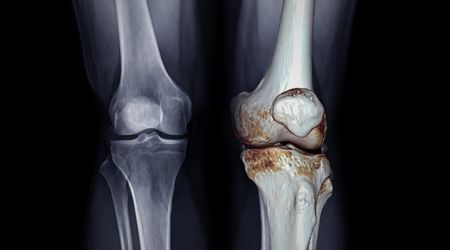

Osteoartrit Tanısı Nasıl Konur?

Kireçlenmenin teşhisi, hastanın öyküsü, fizik muayene bulguları ve bazı görüntüleme yöntemleriyle konur:

- Radyografi (X-ray): Kıkırdak kaybı, eklem aralığında daralma, kemik çıkıntıları

- MR: Yumuşak doku ve kıkırdak durumu hakkında detaylı bilgi

Kireçlenme İlerlerse Ne Olur?

Kireçlenme tedavi edilmediğinde eklem kıkırdağı tamamen aşınabilir. Bu da eklem aralığının daralmasına, kemiklerin birbirine sürtünmesine ve şiddetli ağrı ile hareket kısıtlılığına yol açar. İleri vakalarda günlük yaşam aktiviteleri zorlaşır ve cerrahi müdahale gerekebilir.